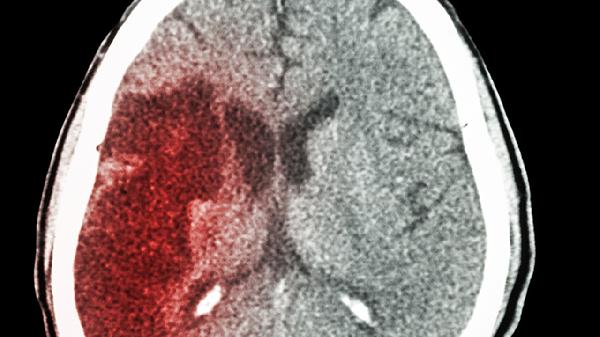

脑出血患者因血肿对脑组织的直接破坏和继发性脑水肿,往往造成不可逆损伤。即便血肿吸收后,原出血区域的神经功能恢复难度较大。脑室出血或出血量超过30毫升的患者预后较差,常伴随认知障碍、运动功能障碍等长期后遗症。但小量出血且未累及关键功能区的患者,经过积极治疗也可能获得较好恢复。